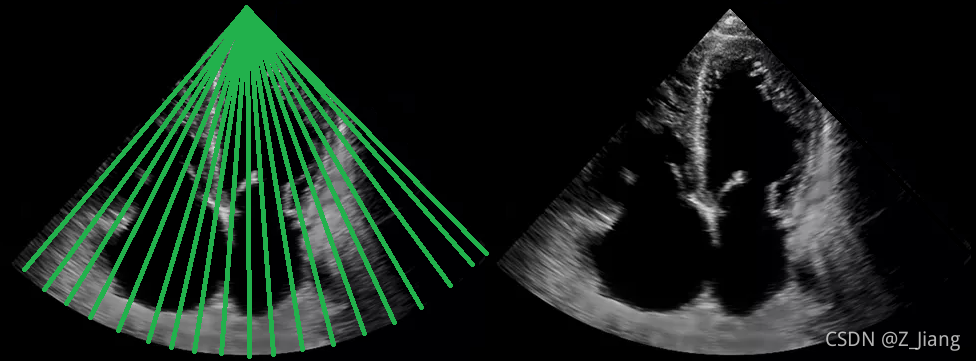

一副二维图通常需要 重复我们仿真的那种发射若干次(下图左绿线所示),才能完成一副成像,如下图绿线所示。

别人的相控阵图像

我们模拟一下上图相控阵探头的二维扫查,直观感受声场能量分布变化;

我们在2D扫查中的beam profile模拟仿真动画